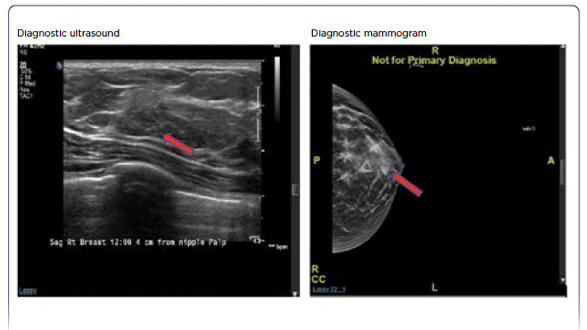

Metastatic Melanoma With Leptomeningeal Disease

Amanda M. Marinova, MS, PA-C, Jennifer L. Reilly, CRNP, BSN, MSN, RN, AANP, Victoria Wong, MS, PA-C, Stephanie Weiss, MD, and Anthony J. Olszanski, MD

January 19, 2021